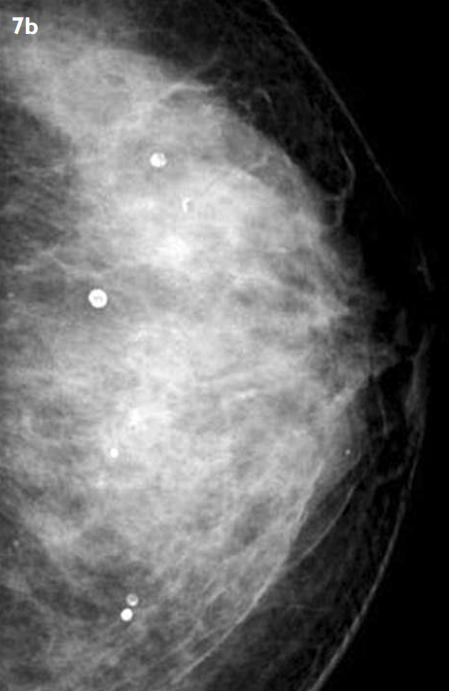

이렇게 밀도가 높은 유방 조직은 유방 촬영술(맘모그래피)에서 하얗게 나타나기 때문에

유방암을 초기에 발견하는 데 어려움이 있을 수 있습니다.

하기 유방 엑스레이(맘모그래피) 사진들로 비교를 해볼께요.

위 사진을 봤을 때, 유방의 치밀도는 오른쪽으로 갈수록 점점 더 밀도가 높아지며, 그에 따라 유방 조직의 특성이 달라집니다.

좌측의 지방유방과 비교했을 때, 가장 우측의 치밀유방은 확실히 눈에 띄게 다르게 보이죠?

이렇게 하얀색으로 나타나는 유방 조직은 암 조직과 구분하기 어려운 경우가 많습니다.

유방촬영술(맘모그래피)에서 유방 석회화는 하얀 점처럼 나타나는 작은 칼슘 침착물을 의미합니다.